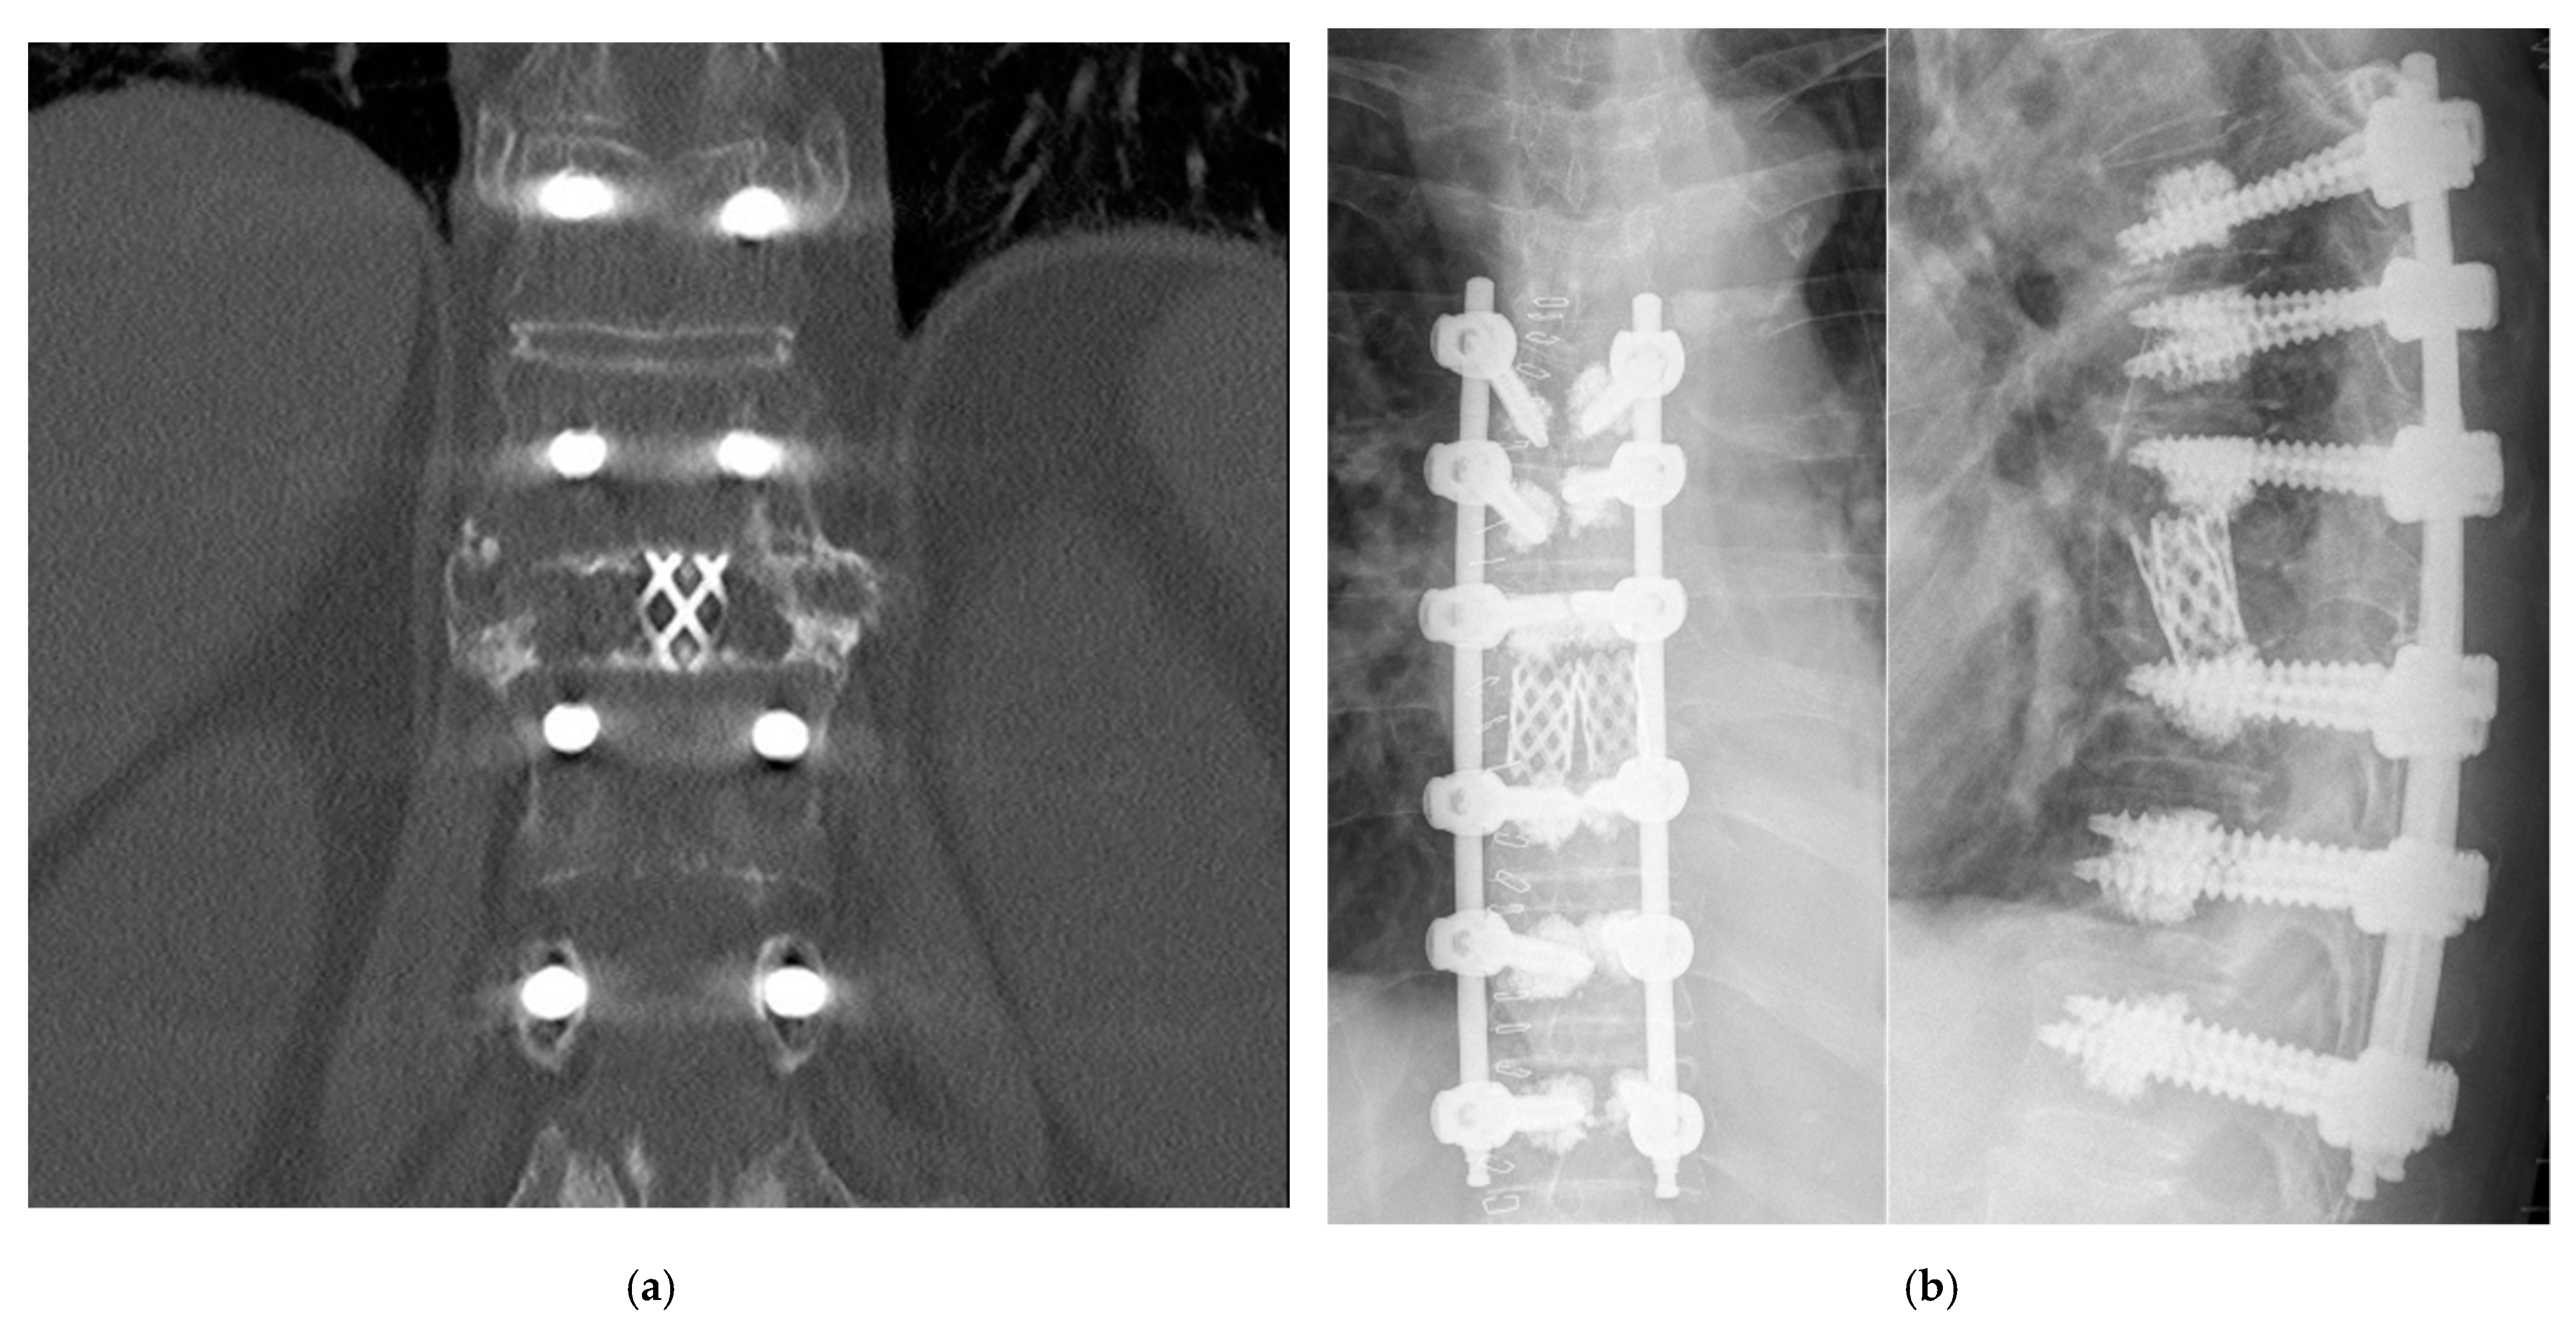

3.3. Radiological Outcome